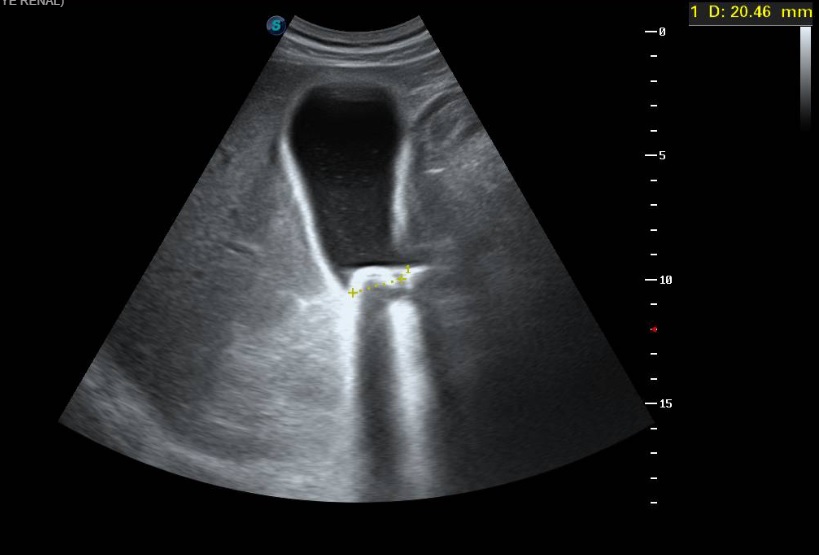

Ecografía clínica a pie de cama: Parénquima hepático y esplénico de ecoestructura preservada. Vesícula biliar marcadamente distendida con imagen hiperecogénica de 2 cm en porción declive compatible con litiasis. Dilatación de la vía biliar intrahepática difusa así como dilatación del colédoco.

La litiasis y la dilatación de la vesícula biliar encontrada en la ecografía clínica no justificaba todo el cuadro, por lo que solicitamos ecografía reglada al equipo de radiología. En ella informan marcada dilatación de la vía biliar intrahepática, con un colédoco de hasta 15 mm, y estructura mamelonada de aproximadamente 7 cm en cabeza pancreática. Se completa estudio con Tomografía Axial Computarizada que confirma masa en cabeza pancreática compatible con adenocarcinoma que condiciona dilatación de la vía biliar retrógrada.